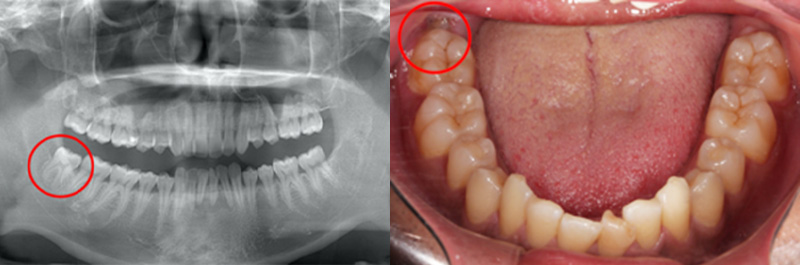

親知らずは、真っ直ぐ歯の並びに沿って生えている場合で、ご自身で歯磨きしやすいときには抜く必要はほぼありません。下のレントゲン写真と口の中の写真の赤丸で囲んである親知らずに関しては、真っ直ぐ生えており、特に虫歯もなく綺麗に磨けているので抜かなくて大丈夫です。